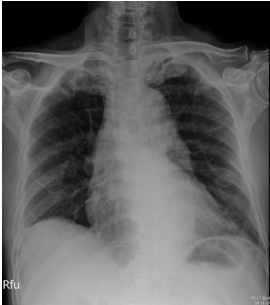

3. 82歲老婦人到院主訴五天來有日趨嚴重的呼吸困難。病史顯示30年前就有醫師告知心臟雜音,因無症狀,未曾有任何治療。近五年來運動耐受逐漸不佳,且偶有突發性悸動及心絞痛,特別在步行樓梯間更加惡化。住院當日清晨3點突然重度呼吸困難,因而急診住院。理學檢查:血壓110/62 mmHg;心跳90/分;頸靜脈怒張。心臟大小正常,但在右上胸骨緣及心尖部有Gr III/VI systolic murmur, S2減輕:其他所見尚無異常。其胸部X光、心臟超音波及心電圖如圖。WBC,5.2 k/micro L;AST,21U/L;CK,111U/L;CK-MB,14.6U/L;Troponin I,0.06 ng/ml。請問下列何項處置最恰當? (A) Percutaneous coronary intervention (B) Aortic valve replacement (C) Nitroglycerin IV infusion at the rate of 15mcg/min (D) Titrate PO carvedilol starting from 3.125 mg and reassess in 3 months (E) Treating with IV digoxin 0.125mg in conjunction with IV bolus Furosemide 20mg and then 20 mg BID

胸部 X 光